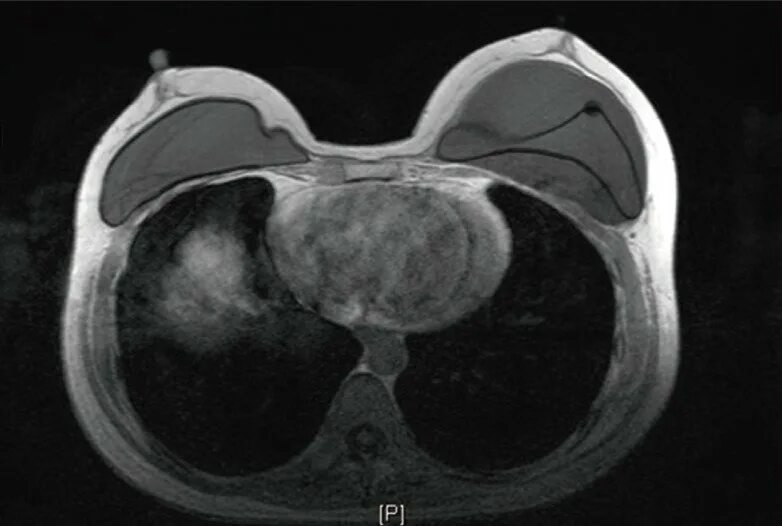

Делают ли кт молочных желез